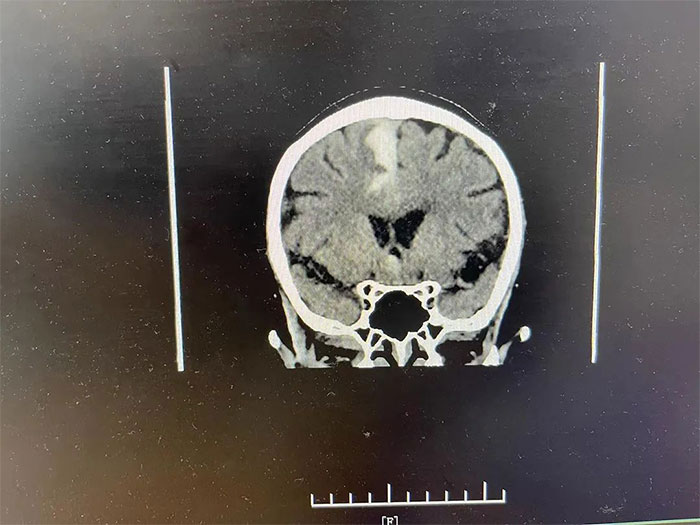

▲ 入院檢查顱內(nèi)仍有出血活動

更令人不安的是,CT檢查顯示,吳阿姨右側(cè)大腦頂葉出血灶較前變化不明顯,提示仍有出血活動,若不及時進(jìn)行干預(yù),隨時都有“決堤”的可能,不僅影響神經(jīng)功能恢復(fù),病情還可能因之進(jìn)一步惡化,甚至危及生命。

▲ 通過治療,出血已基本吸收